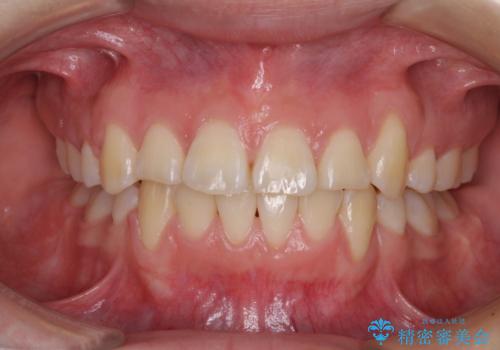

歯列はきれいに整いますが、歯肉ラインは治療前の歯肉の位置を踏襲します。

特に八重歯であった歯は歯冠が長く見えますので、改善を希望される場合には、歯肉移植術を行う必要があります。